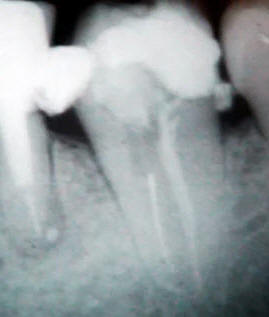

Secuencia técnica para eliminar instrumentos rotos en el conducto radicular

•  Una radiografía periapical preoperatoria y

•  una excelente visión del cabo fracturado  por medio del microscopio dental.